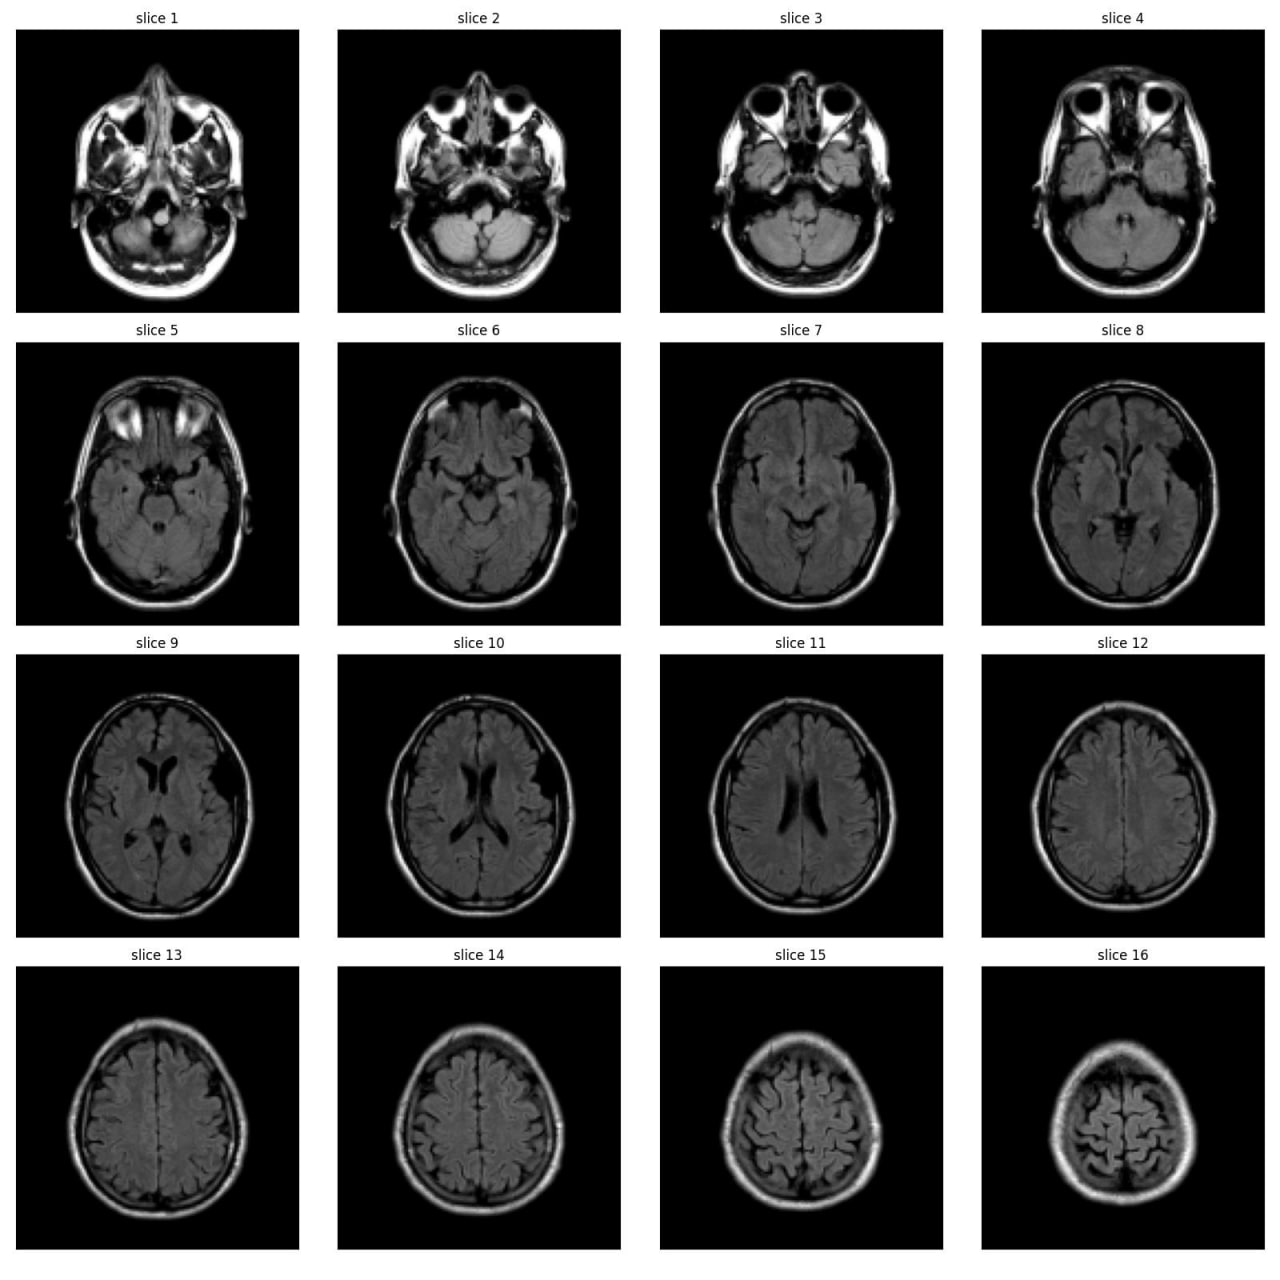

As part of the JIM3 team, I competed in the IAAA competition, which involved a dataset of 4,000 MRI images, with only 500 labeled as abnormal. The competition aimed to develop a model for patient-level abnormality classification. We utilized various models, including EfficientNet, DenseNet, ResNet, custom CNN models, and Vision Transformers (VIT), along with different preprocessing techniques. Working closely with a medical team, we converted subject-level annotations into slice-level annotations for more effective model training. Despite discovering inconsistencies in the test set and normal cases after the competition, we secured 17th place among over 100 teams. The technical team is currently working on a paper using the annotated data from this project.